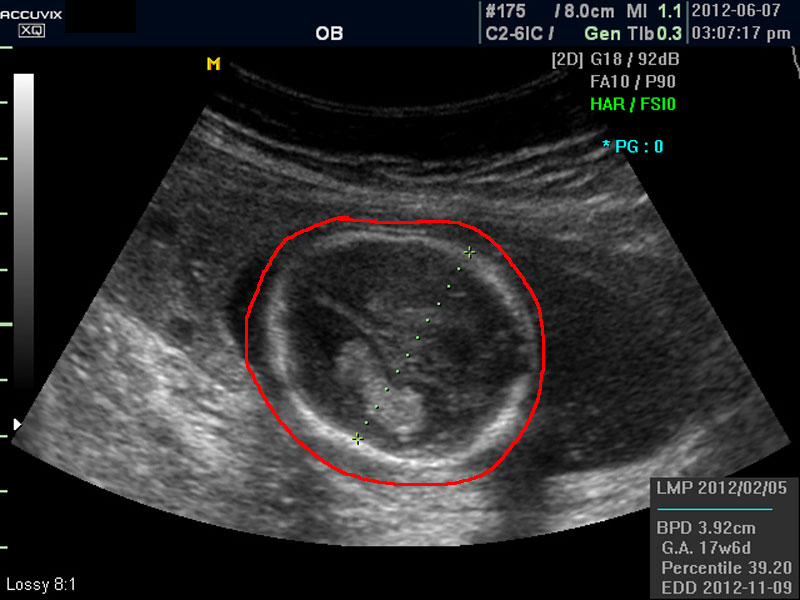

위 사진에서 빨간 동그라미로 표시한 부분이 태아의 머리를 위에서 내려다 본 수평 단면입니다.

하얗게 보이는 것은 뼈이고 내부에 검게 보이는 것은 뇌실에 고인 척수액 부분이며 내부의 하얀 부분은 뇌조직과 뇌실 내 맥락막이라고 하는 것입니다.

4. BPD

Biparietal Diameter의 약자로 머리를 위에서 보아서 양쪽 옆통수에서 반대쪽 옆통수까지의 길이입니다.

이는 임신 중기부터 후기까지 태아의 발육을 판단하는 중요한 지표이며 태아의 체중을 예측하는 데 쓰이는 지표 중 하나입니다.